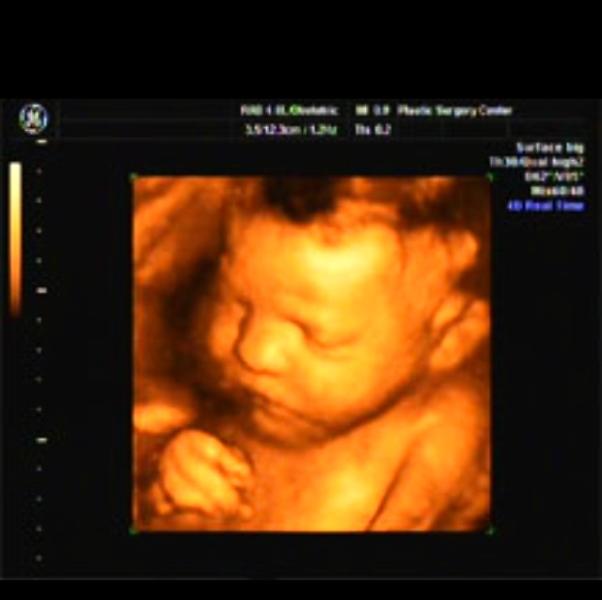

Мамочки, а Вы делали 3D узи? Как вам результат? Наш малыш спал))) даже преддоженный горячий шоколад нам не помог, единственное в конце начал хмуриться)) и сосать пальчик)

мы тоже ходили на 3д.ходили после 30 недель,поэтому наша ляля была уже довольно крупненькой и видно было похуже.но личико разглядели,хоть она и закрыла глазки рукой.а в конце она...улыбнулась!😻вот это было круто,зафоткали нам этот момент на память-успели)))радовались мы с мужем, как дети👍